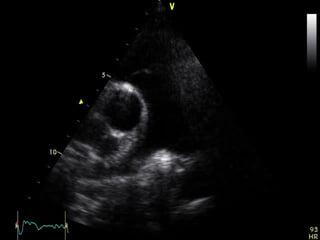

From the PLA orientation, a 90° clockwise rotation of

the transducer with superior and inferior

transducer manipulations permits delineation of the

parasternal short axis (PSA) views:

-At the base (aortic valve) view

Parasternal short axis

70°to 110° clockwise

a 90° clockwise rotation

At the basal (aortic valve) level, the right atrium, septal

and anterior leaflets of the tricuspid valve, right

ventricular free wall, right ventricular outflow tract,

pulmonic valve, main pulmonary artery, and left

atrium can be seen "surrounding" the centrally

oriented aortic valve.

All three leaflets of the aortic valve may be identified,

forming a "Y" configuration during ventricular

diastole and "upside-down triangle" during

ventricular systole

From the PLAorientation, a 90° clockwise rotation of the transducer with superior and inferior transducer manipulations permits delineation of the parasternal short axis (PSA) views: -At the base (aortic valve) view -Mid (mitral valve ) view -Mid ( papillary muscle) view -And apical levels view Parasternal short axis 70°to 110° clockwise

Parasternal short axis a90° clockwise rotation

At the basal(aortic valve) level, the right atrium, septal and anterior leaflets of the tricuspid valve, right ventricular free wall, right ventricular outflow tract, pulmonic valve, main pulmonary artery, and left atrium can be seen "surrounding" the centrally oriented aortic valve. All three leaflets of the aortic valve may be identified, forming a "Y" configuration during ventricular diastole and "upside-down triangle" during ventricular systole